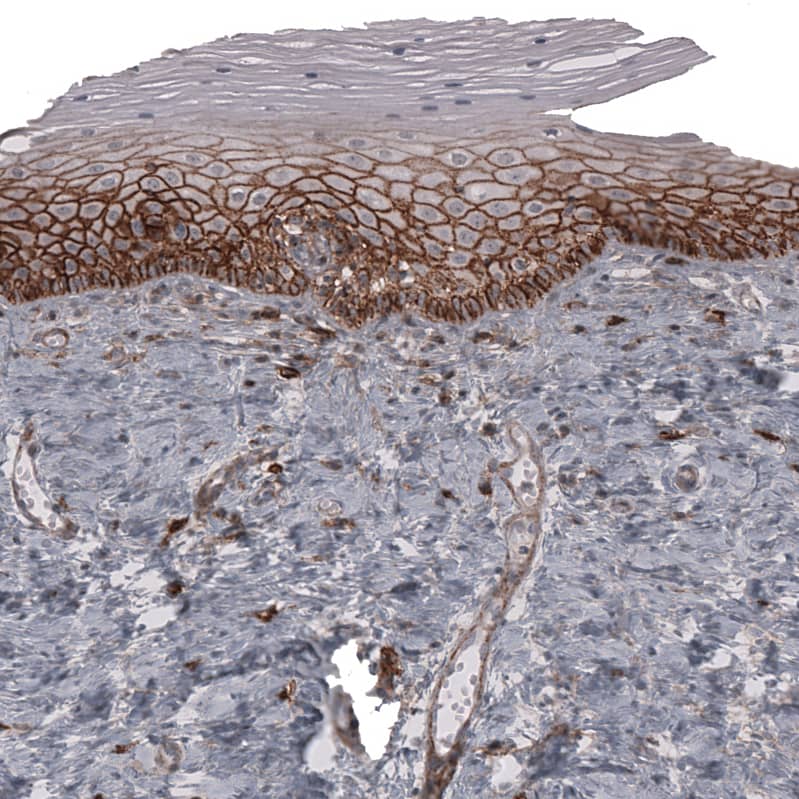

Staining of human uterine cervix shows strong membranous positivity in squamous epithelial cells.